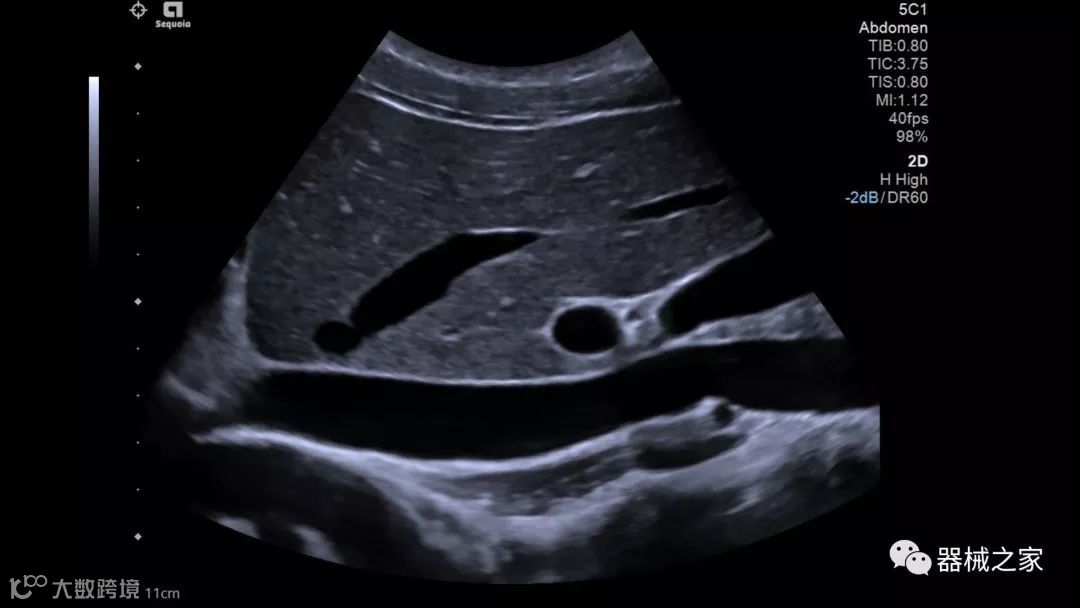

Baptist Health South Florida成为去年秋天西门子医疗保健公司Acuson Sequoia的首个商业安装网站。该系统将有助于增强胃肠病学,初级保健和减肥专业的成像能力。Sequoia可实现高分辨率成像,自动适应患者的体型和个人身体特征,有助于更加自信的诊断。它适应患者的组织密度,刚度和超声波束吸收的生物声学变化。这使得系统可以穿透高达40厘米而不会因衰减回波信号而导致图像质量下降。

Acuson Sequoia